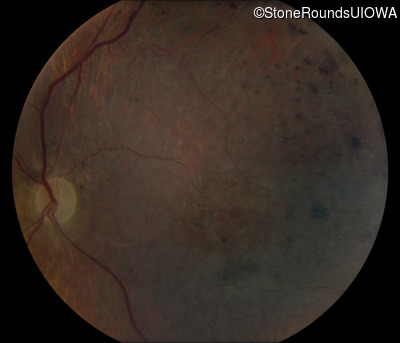

This 41 year old man first came to medical attention at age 18 months when exotropia and amblyopia of his right eye were discovered. At age 11 vitreous strands and retinal vascular sheathing were seen. He has had poor night vision and constricted visual fields since his late teens. Later, at age 44 a traction retinal detachment was noted in his left eye and was treated with a scleral buckle.

Age at visit: 41 years